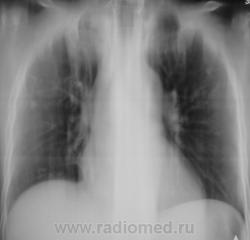

БОМЖ.

Контроль через 6 мес.